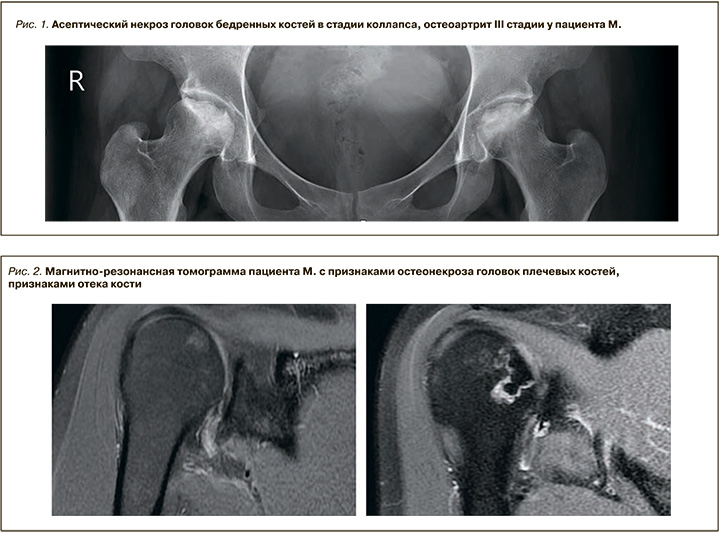

В 2016 г. у пациента были отмечены ограничение движений и боли в области тазобедренных суставов, при обследовании выявлены асептический некроз головок бедренных костей в стадии коллапса и остеоартрит III стадии по Келлгрен–Лоуренс (рис. 1). Было проведено тотальное эндопротезирование тазобедренных суставов с обеих сторон без осложнений в послеоперационном периоде с хорошим клиническим эффектом (болевой синдром разрешился полностью, подвижность восстановилась в полном объеме).

Верифицирован остеонекроз головок плечевых костей. Пациента беспокоили интенсивные (9 и 7 баллов по числовой рейтинговой шкале) боли и ограничение подвижности плечевых суставов. На МРТ плечевых суставов было выявлено наличие очагов остеонекроза плечевых костей, окруженных зоной отека костного мозга размером 2,0×1,4 см слева и 1,7×0,9 см справа (рис. 2).